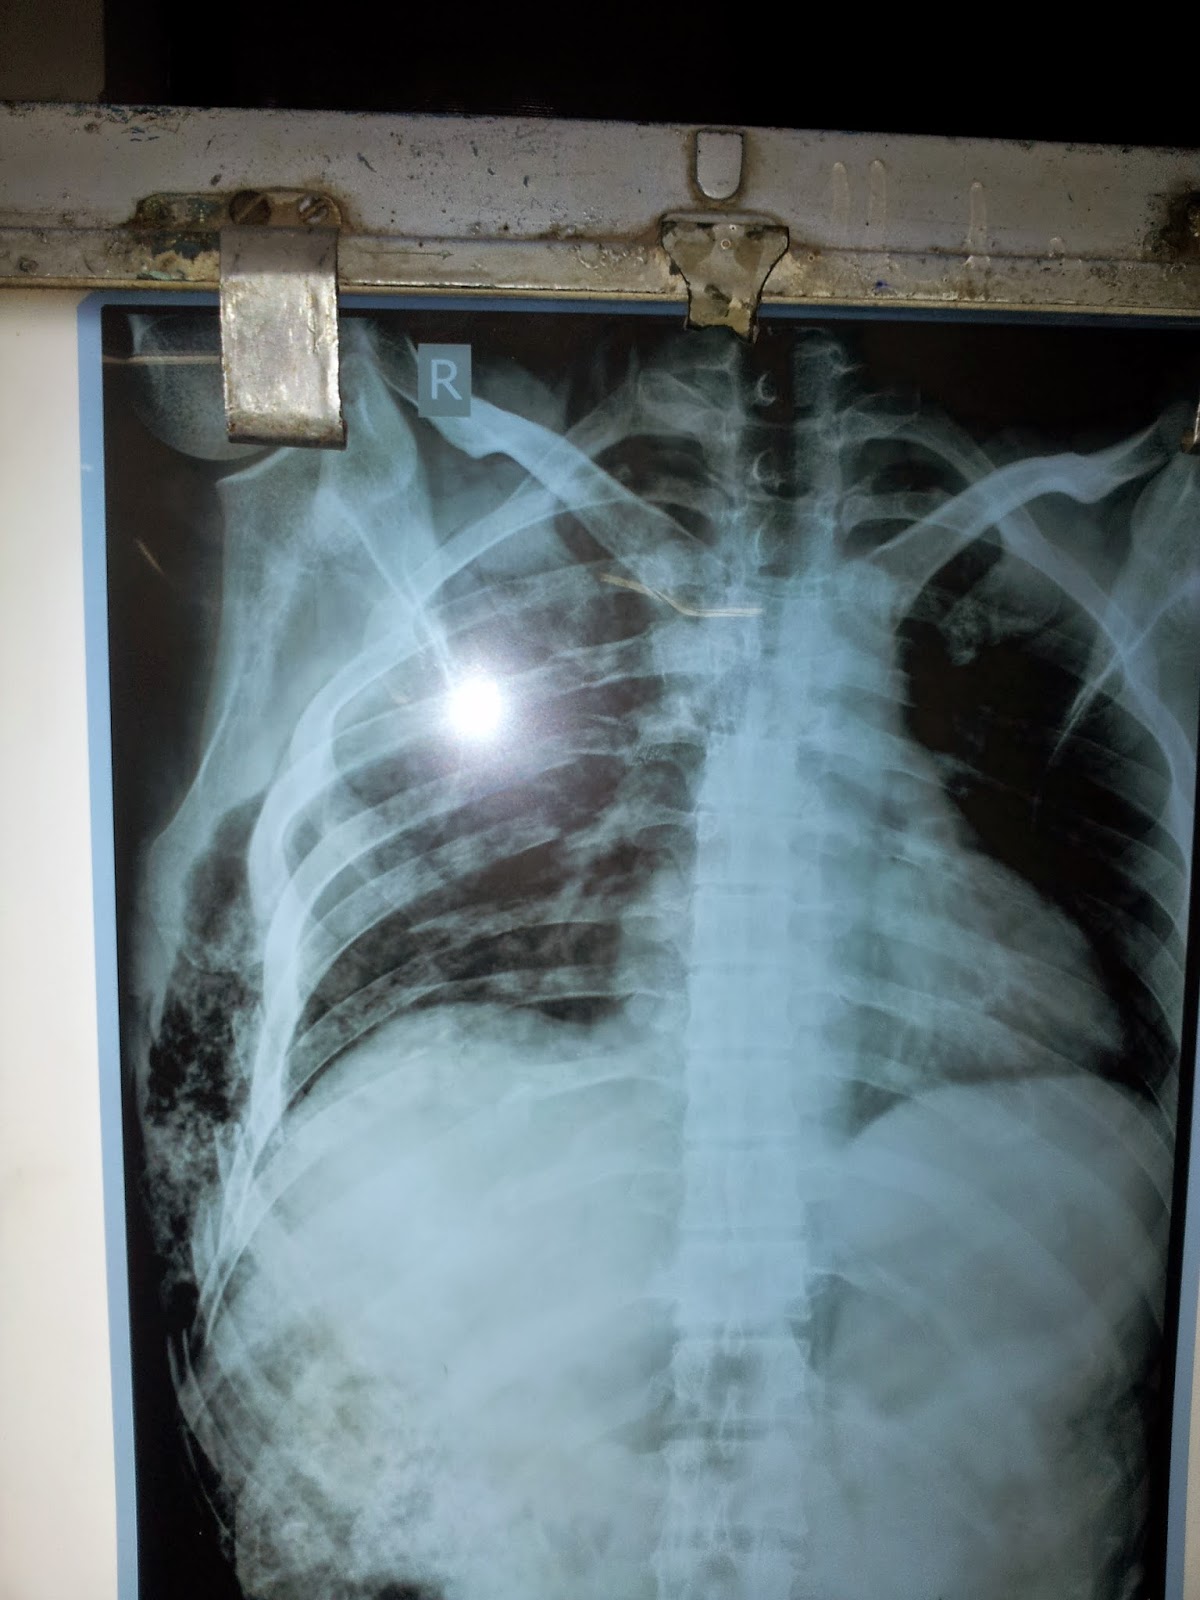

A Chest Xray of a Patient with Rib Fractures and Pleural Effusion and Rib Fracture Emphysema Web the chest wall is highly innervated by pairs of intercostal nerves traveling along the inferior border of each. Web this article provides an overview of the common and important chest injuries that the anesthesiologist may. Web in the grade 4, trauma due to rib fracture (50 %) was detected as the most common cause. Web pneumonia is an important. Rib Fracture Emphysema.

a Chest radiograph Right subcutaneous emphysema associated with Rib Fracture Emphysema Web the chest wall is highly innervated by pairs of intercostal nerves traveling along the inferior border of each. Web in the grade 4, trauma due to rib fracture (50 %) was detected as the most common cause. Web pneumonia is an important complication of the acute phase of rib fracture and can even occur after a minor rib fracture,. Rib Fracture Emphysema.

Chest Xray (Haemothorax/Pneumothorax/Surgical Emphysema/Rib fracture Rib Fracture Emphysema Web this article provides an overview of the common and important chest injuries that the anesthesiologist may. Web subcutaneous (or surgical) emphysema is the presence of gas in the subcutaneous soft tissues, which may be detected clinically by swelling of the affected area and crepitus on palpation. Web the chest wall is highly innervated by pairs of intercostal nerves traveling. Rib Fracture Emphysema.